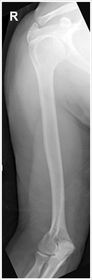

| AP Humerus | humeral epicodyles not in profile radial head, neck and tuberosity to not superimpose ulna arm is externally rotated (greater tubercle in profile) |

| Lateral Humerus | over rotation places the humeral head within the field of the chest |

| Lateral Humerus | epicondyles are not perpendicular humerus is internally rotated (lesser tubercle is in profile medially) overrotation |

| AP Humerus | ANATOMY: entire humerus: shoulder -> elbow CRITERIA: greater tubercle in profile - hand externally rotated humeral epicondyles are parallel to IR POSITIONING: CR perpendicular @ midhumerus |

| Lateral Humerus | ANATOMY: entire humerus: shoulder -> elbow CRITERIA: lesser tubercle in profile - arm internally rotated epicondyles superimposed POSITIONING: pt rotated 15-20 degrees from PA to get arm lateral and away from chest - flex elbow 90 degrees CR perpendicular @ midhumerus |